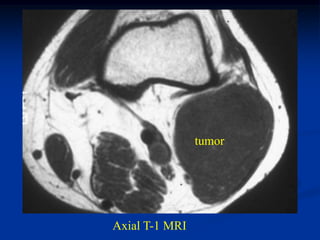

Case #1191

24 year female with

angiolipoma anterior

thigh

Sagittal T-1 MRI

Axial T-1 MRI

Coronal T-2 MRI

Sagittal gad

contrast MRI

Case #1191 24 yearfemale with angiolipoma anterior thigh Sagittal T-1 MRI

• 90.

• 91.

• 92.